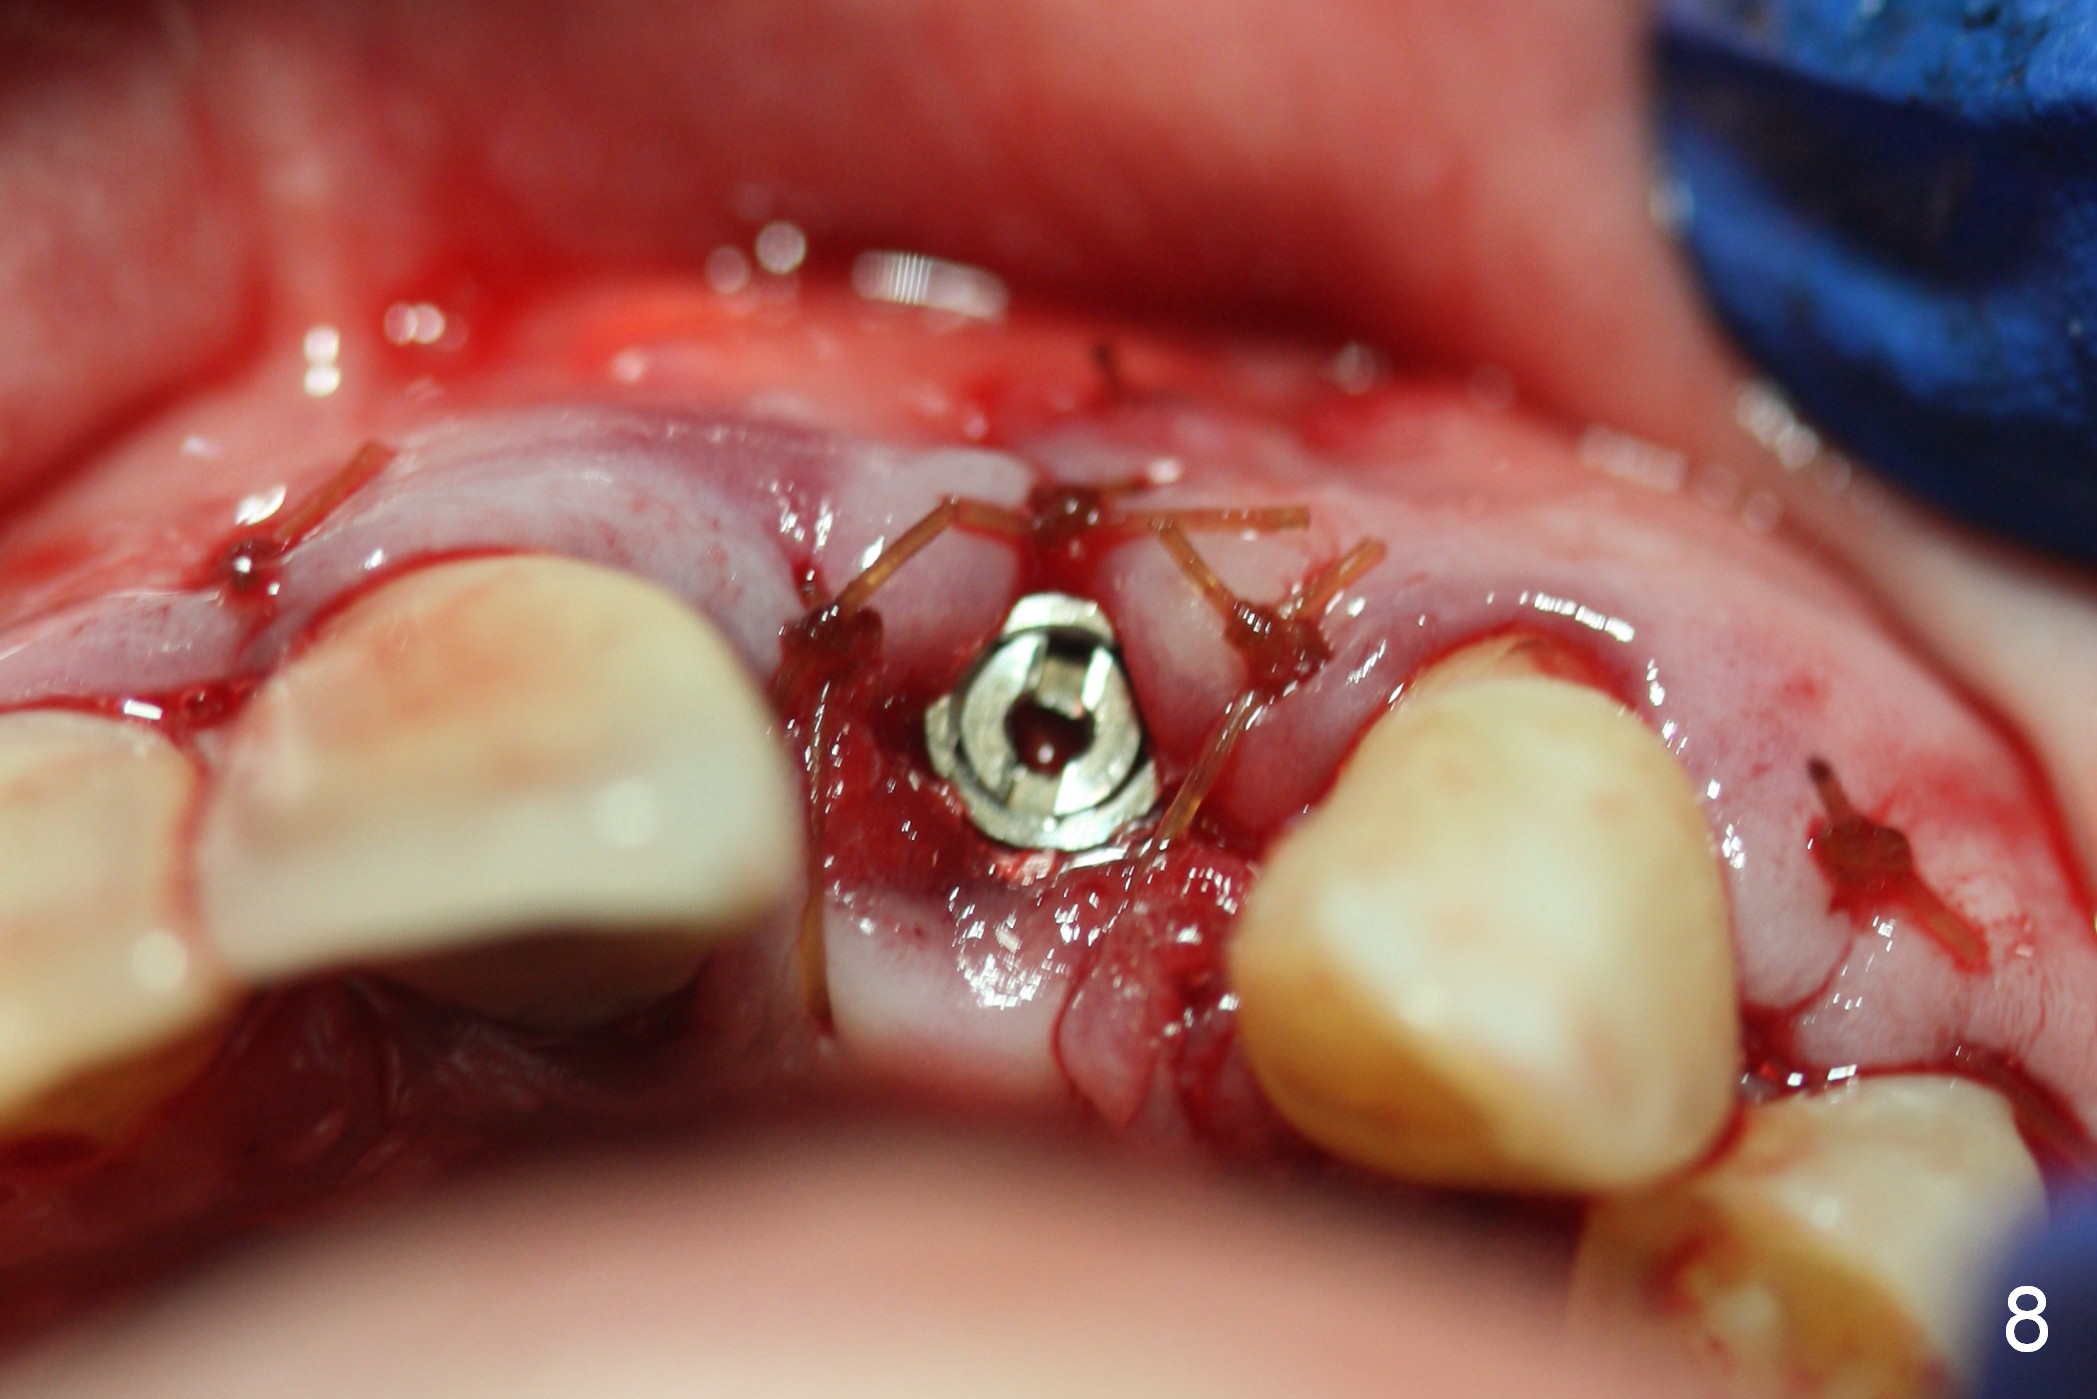

The 57-year-old lady does not like the crown at the site of #10 immediately when it is cemented (Fig.1). When the upper lip is retracted, it appears that the implant is immediately underneath the gingiva (Fig.2 *). It is slightly tender when palpated. The patient refuses CBCT. When the buccal flap is raised, the implant is found to be exposed buccally (Fig.3). When it is removed, the coronal portion of the palatal wall is thin (Fig.4). It appears that there is bone in the mid and apical thirds of the palatal wall, where an osteotomy is initiated using a 1.2 mm pilot drill. When the latter reaches 18 mm from the crest, the nasal floor appears to be perforated. The latter is confirmed by PA (Fig.5). As the osteotomy are increasing in diameter, force is applied as palatally as possible without perforating the palatal wall too much. When a 3.5x20 mm implant is placed (30 Ncm), it is palatal to the labial wall. The defect is filled by allograft and Osteogen, covered by long termed resorption membrane. The buccal flap is sutured (Fig.7). A proposal to place gingival graft is rejected. The implant is shown to have been positioned more or less normally (Fig.8). A removable temporary appliance is fabricated. Periodontal dressing is applied.